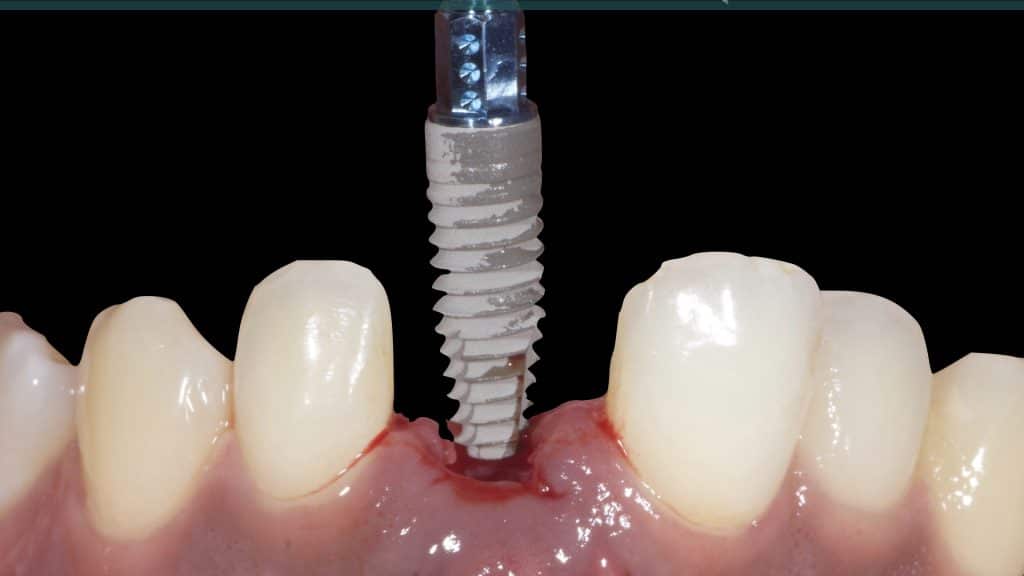

A 27-year female patient with dislodged Resin bonded FPD. She had that FPD for past few years, it had metal wings on palatal surfaces of UR1 and UL2 and a post like metal extension into the root canal of UL1. There was gingival abscess due to fractured root segment most probably due to extended metallic post like structure. Immediate implant placement (IIP) and Immediate restoration (IR) was planned for this patient.

20 days post-op after suture removal